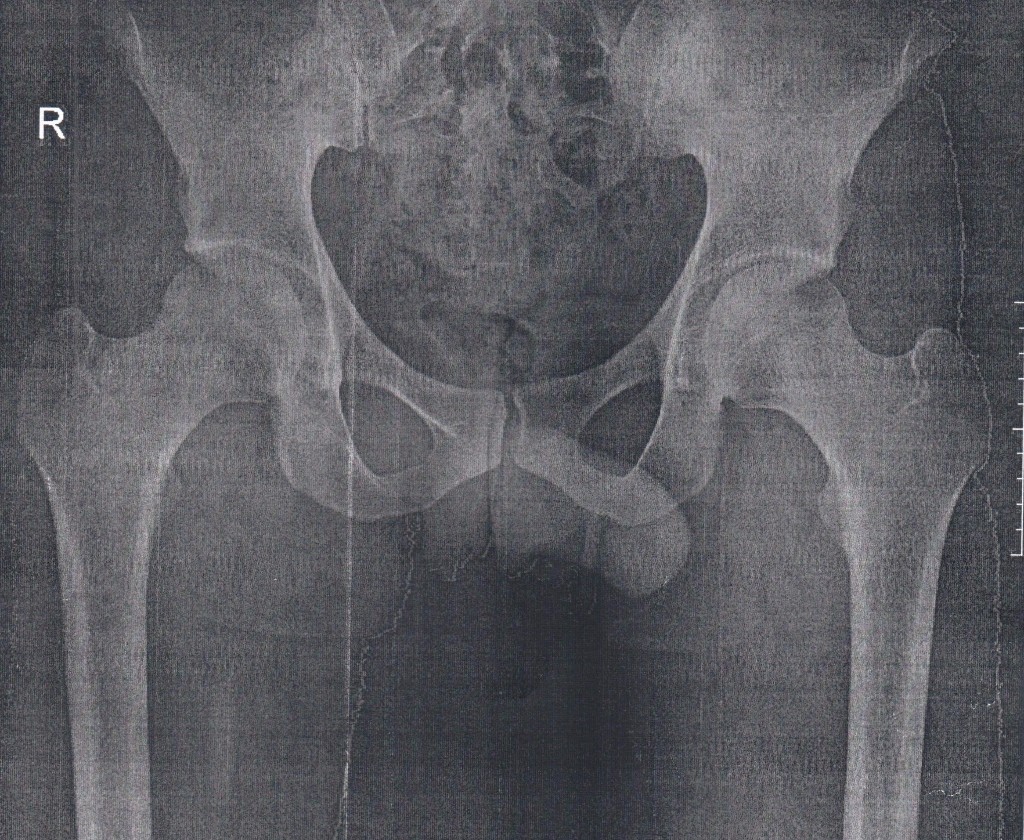

Рентген ТБС: Нормальные показатели